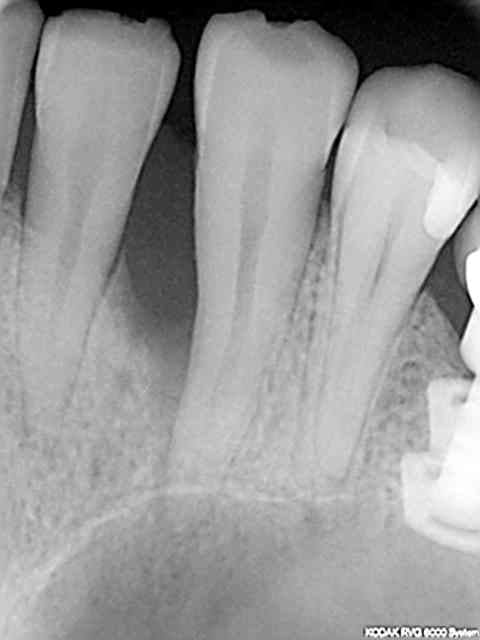

rvg avant endo et 3 mois après endo retouche occlusale et rtr +prf on voit le "fut.." en 15 !

c'est le coté droit qui a été équipé en dernier c'est de ce coté que commence les problèmes cad fenestration en haut fracture dentaire en bas.